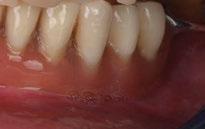

SW 5.2, Dentsply Sirona) (Figuras 22-27), la cual fue materializada en dos tipos de materiales a partir de bloques cerámicos IPS Empress CAD y cerámica vítrea de disilicato de litio IPS E.max CAD (Figuras 28-30)

Finalmente, las restauraciones se cementaron adhesivamente (Figuras 31-35). En las piezas 16 y 17 se realizaron restauraciones cementoatornilladas como última fase de tratamiento. Se recomendó al paciente una férula de protección superior la cual fue elaborada mediante un flujo de trabajo digital (Figura 36)

El tratamiento restaurador aditivo dentro de la rehabilitación oral completa puede ser un desafío clínico para el profesional. Este reporte de caso clínico demuestra que la fabricación de restauraciones indirectas CAD/CAM proporciona

estética y funcionalidad. Marchesi y cols 2021 determinaron las tendencias actuales de usos clínicos del material empleado en este caso en los dientes anteriores, al ser una cerámica feldespática reforzada con leucita presentando una fase vítrea (55% a 70%) convirtiéndose en uno de los materiales cerámicos más traslúcidos y estéticos usados para restauraciones adhesivas parciales con éxito y vida útil en la cavidad oral. Esto coincide con lo afirmado por Nejatidanesh et al 2018 (13) en su estudio retrospectivo sobre carillas con bloques Empress CAD, donde se evaluó el rendimiento clínico de las restauraciones preservando, en mayor cantidad, la estructura dental con tratamientos conservadores y resultados a largo plazo.

1. En la rehabilitación oral aditiva con el sistema chairside, las restauraciones CAD/CAM se adaptan a las necesidades clínicas sumando el uso de los materiales restauradores con propiedades físicas y mecánicas ideales personalizadas para cada paciente.

2. La elección del material restaurador, las preparaciones dentales mínimamente necesarias, la digitalización y el diseño de las restauraciones son pasos claves en el sistema chairside para lograr una correcta adaptación a las estructuras dentales con el ajuste preciso a nivel de los márgenes.

3. El material restaurador con cerámica feldespática reforzada con leucita ha mostrado estética y emulación de naturalidad, por lo que lo definen como un material

de primera elección para el sector anterior. Para el sector posterior una cerámica feldespática con refuerzo de disilicato de litio es una opción muy recomendable para el éxito de este tratamiento aditivo restaurador.